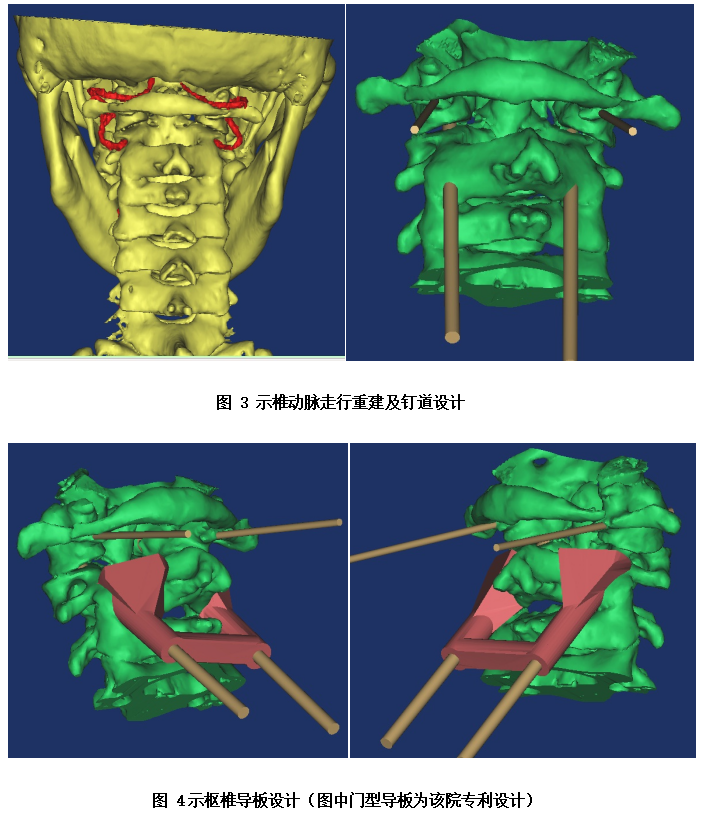

面对患者和家属的信任、期待,岳池中医院骨伤科脊柱团队也高度重视该手术。为了减轻患者痛苦及预防相关并发症,促进患者快速康复,经骨伤科全科讨论,决定由脊柱专业组周中伦副主任医师及陈仕文主治医师共同主刀为患者进行手术治疗。在完善相关术前检查排除手术禁忌的条件下,该团队为患者精心设计了手术方案。且为进一降低手术风险,陈医师发挥自已的专业特长,为患者进行了上颈椎的3D模型重建及钉道设计;考虑到枢椎的椎动脉高跨情况,特别为患者设计并制作了枢椎的3D打印导板以引导植入螺钉。

当充分完成术前准备后,于上月下旬,在麻醉科、手术室等医务人员的密切配合下,周医师及陈医师上台为杨阿姨实施了该手术。经过精心操作和不懈努力,成功为患者行了3D打印导板引导下的颈椎后路寰枢椎椎弓根螺钉内固定及取髂骨寰枢植骨融合术,术中患者出血少,手术取得圆满成功。

据医院骨伤科学科带头人刘志勇主任医师介绍,该手术难度和风险极大,采用传统徒手置钉过程中,任何轻微误差均可能导致患者椎动脉破裂大出血或者损伤脊髓导致高位截瘫可能,以前在全省甚至全国大多数医院开展均较少,但我院利用3D打印技术进行术前模拟手术,术中利用3D打印置钉导板的辅助下实现了快速精确置钉,为患者脊柱提供了更强的稳定性和更高的安全性,从而获得了更好的疗效。此例手术的成功开展填补了县域内此类手术的空白,标志着岳池县中医医院脊柱外科专业的诊疗水平跨越至新的更高层次,达到省内先进水平。